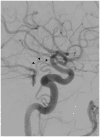

In this review article, we summarized the current advances in rescue management for reperfusion therapy of acute ischemic stroke from large vessel occlusion due to underlying intracranial atherosclerotic stenosis (ICAS). It is estimated that 24-47% of patients with acute vertebrobasilar artery occlusion have underlying ICAS and superimposed in situ thrombosis. These patients have been found to have longer procedure times, lower recanalization rates, higher rates of reocclusion and lower rates of favorable outcomes than patients with embolic occlusion. Here, we discuss the most recent literature regarding the use of glycoprotein IIb/IIIa inhibitors, angioplasty alone, or angioplasty with stenting for rescue therapy in the setting of failed recanalization or instant/imminent reocclusion during thrombectomy. We also present a case of rescue therapy post intravenous tPA and thrombectomy with intra-arterial tirofiban and balloon angioplasty followed by oral dual antiplatelet therapy in a patient with dominant vertebral artery occlusion due to ICAS. Based on the available literature data, we conclude that glycoprotein IIb/IIIa is a reasonably safe and effective rescue therapy for patients who have had a failed thrombectomy or have residual severe intracranial stenosis. Balloon angioplasty and/or stenting may be helpful as a rescue treatment for patients who have had a failed thrombectomy or are at risk of reocclusion. The effectiveness of immediate stenting for residual stenosis after successful thrombectomy is still uncertain. Rescue therapy does not appear to increase the risk of sICH. Randomized controlled trials are warranted to prove the efficacy of rescue therapy.